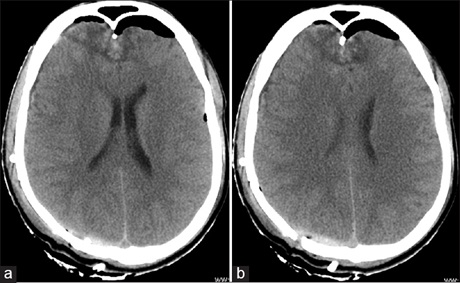

The "CT Comma Sign" in Concurrent Extradural and Hyperacute Subdural Hematomas is Revisited

Extradual hematoma (EDH) is the collection of blood between the inner skull table and dura, and appears as a biconvex‑lens shape on imaging.[1,2] In comparison to EDH, the subdural hematoma (SDH) is a collection of blood between the dura and arachnoid membrane and it has a biconcave‑lens shape on imaging.[1,3] In the acute stage, most of these hematomas present as hyperdense lesions on computerized tomography (CT) images.[1‑4] In rare circumstances, a patient can have acute extradural hematoma and subdural hematoma adjacent to each other on the same side with a characteristic imaging appearance.[5,6]

A 26‑year‑old male patient sustained head injury in a road traffic accident and presented 6 hours after to the emergency department. The patient was unconscious from the time of injury and had multiple episodes of vomiting. There was no history of seizures or nasal/ear bleeds. His general and systemic examination was unremarkable. Neurologically, he had altered sensorium [Glasgow coma score (GCS)‑E1V2M5]. Pupils were bilaterally equal and reactive to light. He moved all four limbs normally. He had multiple abrasions over face and scalp.